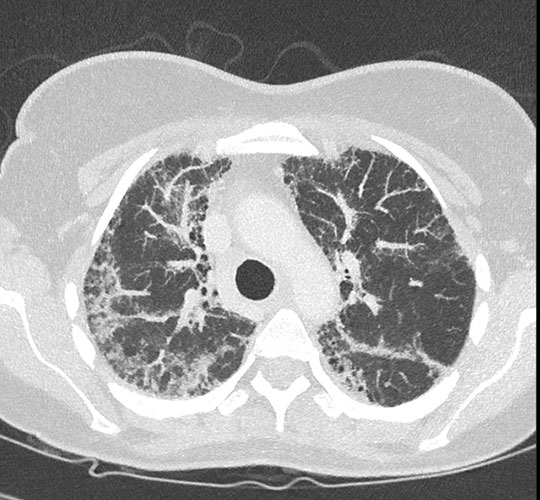

Insbesondere zur Klärung von Knochen- oder Lungengerüstveränderungen findet diese Methode in der Rheumatologie häufig Anwendung.

Eine interstitielle Lungenerkrankung bei rheumatoider Arthritis mit deutlich entzündlicher Verdichtung des Lungengewebes: